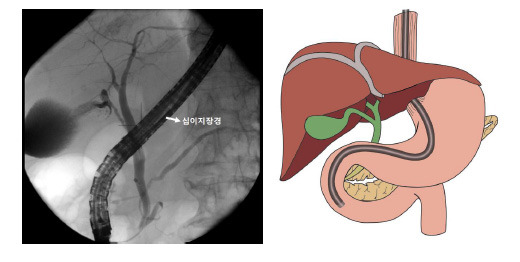

이때 시술했던 환자분은 40대 초반의 여성분으로, 우리가 흔히 쓸개라고 부르는 담낭 내의 돌이 담낭관을 통해 담도로 내려와 담관에 돌이 생긴 경우였다. 십이지장은 1부부터 4부까지 4군데로 나뉘며, 2부에 유두부라고 불리는 담관의 입구가 위치한다.

images2.jpg 십이지장,췌장,담도의 모식도

췌담도 내시경은 일반 내시경과 달리 렌즈가 내시경 앞이 아닌 내시경 옆에 위치하여, 십이지장으로의 내시경 삽입 또한 일반 내시경보다 어려운 내시경이다. 처음 1년간 전임의를 하면서 위내시경과 대장내시경을 배우고, 지원자에 한해서 2년째에 췌담도 내시경을 배우게 된다. 렌즈가 옆에 있기 때문에 내시경을 삽입한 후에도 초보자는 전후좌우를 파악하는 것이 쉽지가 않다. 췌담도 내시경으로 유두부를 관찰한 후 담관 입구로 생각되는 부위에 카테터 (catheter)라고 불리는 얇은 관을 집어넣은 후 관 내부에 유도철선 (가이드와이어, guidewire)을 삽입하여 담관에 유도철선을 삽입하면 영어로 cannulation, 한국말로 삽관이라고 하는 과정이 끝나게 되며, 삽관이 되면 췌담도 내시경은 대부분 성공하게 된다. 쉽게 말해서 환자를 치료할 때 그 환자의 질병을 진단하는 것이 무엇보다 중요한 것과 마찬가지다. 하지만, 유두부는 담관뿐만 아니고 췌장의 소화액이 내려오는 췌관의 입구도 위치하는 곳이며, 담관과 췌관의 입구는 불과 몇 mm 만 떨어져 있는 경우도 많아 담관으로의 선택적 삽관이 잘 안 되는 경우가 종종 발생한다.